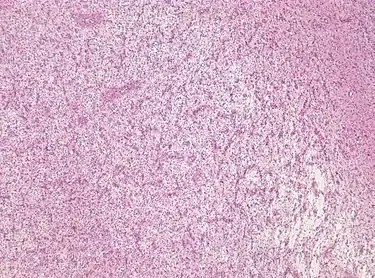

For further confirmation, the clinicians require biopsy and immunohistochemical staining of the resected tumor after surgery. The infiltrative AG cells display positive results for several immunostainings, especially the glial fibrillary acidic protein (GFAP) and epithelial membrane antigen (EMA).[1] Clinicians also observe a specific dot-like pattern from the stained EMA photomicrograph.[3] Other specific AG immunohistochemical tests include Ki-67 proliferative marker, neurospecific nucleoprotein (NeuN), protein 53, synaptophysin (Syn), oligodendrocyte transcription factor-2 (Olig-2) and creatine kinase (CK).[3] In the 2016 WHO classification of CNS tumors, AG is characterised as GFAP-positive, NeuN-positive and low Ki-67 proliferative rate with a perivascular growth pattern.[13]